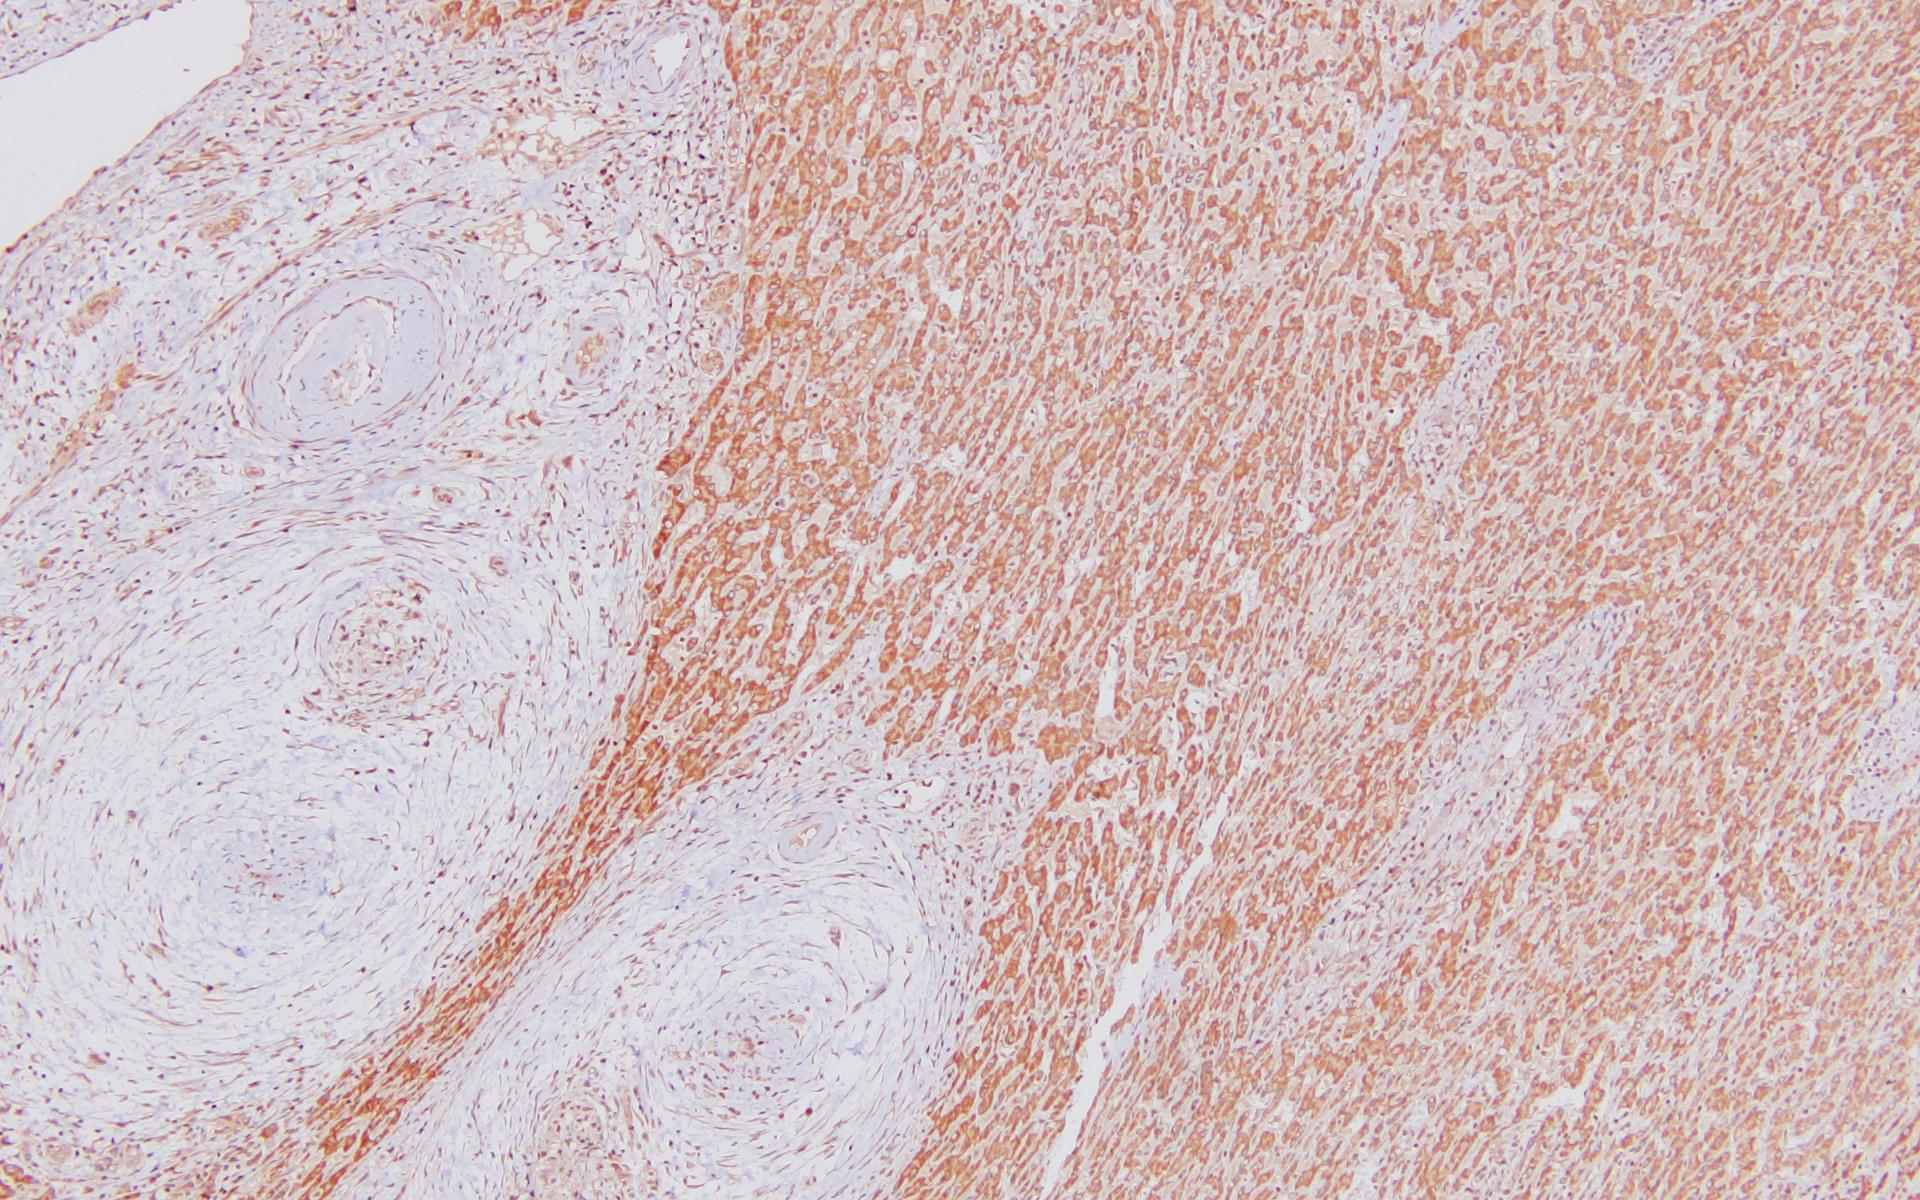

SUCLA2

Anti-SUCLA2 Polyclonal Antibody